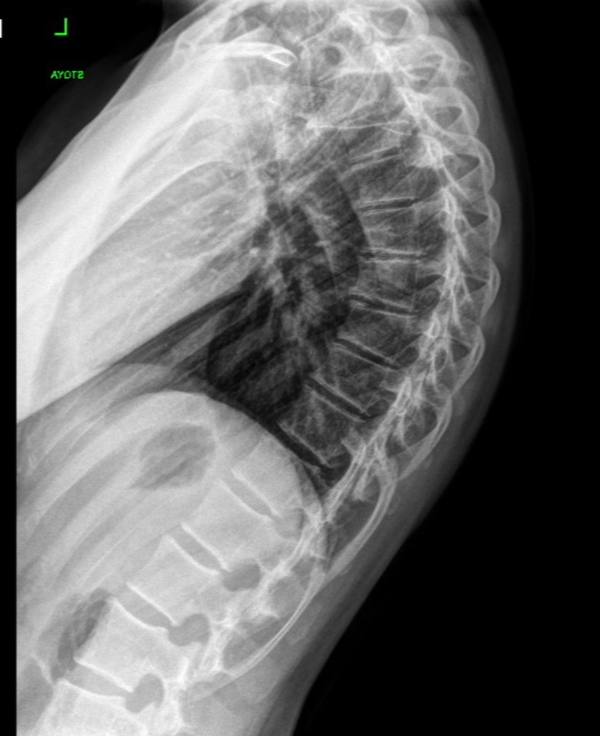

Возраст пациента: 19 лет

Угол кифоза: 65°

Работа с гиперкифозом это всегда работа в долгую, это изменение и центра тяжести тела и паттерна дыхания, а также много осознанности для удержания позы с меньшим углом кифоза в течение дня.